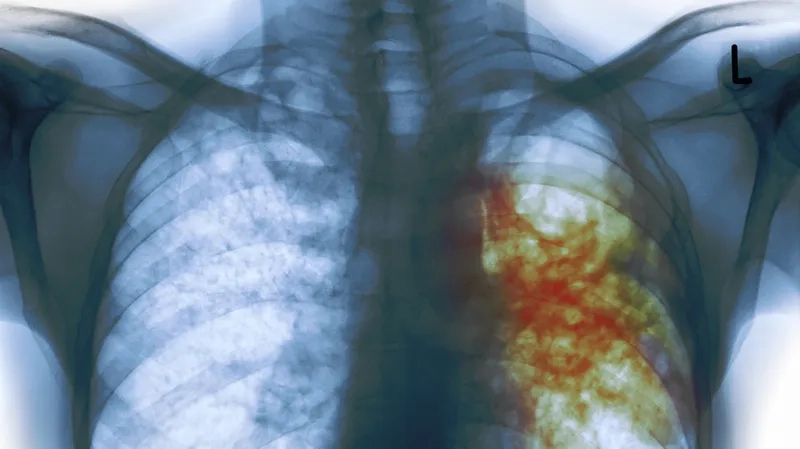

What the symptoms of tuberculosis look like